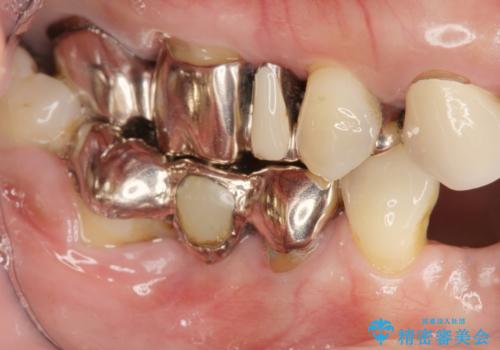

歯周病 全顎治療

- 前歯の見た目、入れ歯による噛めないことの改善を求めて来院されました。

検査により全顎的な歯周病治療、欠損のインプラント補綴、根管治療が必要な状態であることをお伝えし、治療を計画します。

全体的な歯周病が認められる場合、歯を失った一部のみの治療となることはほぼありません。

失ってしまった機能を回復し、今後歯を失わないよう残せる歯に歯周病治療を行い、安定した咬合を確立することで長期的に問題なく噛めるような口腔内環境を達成できるようになると考えます。